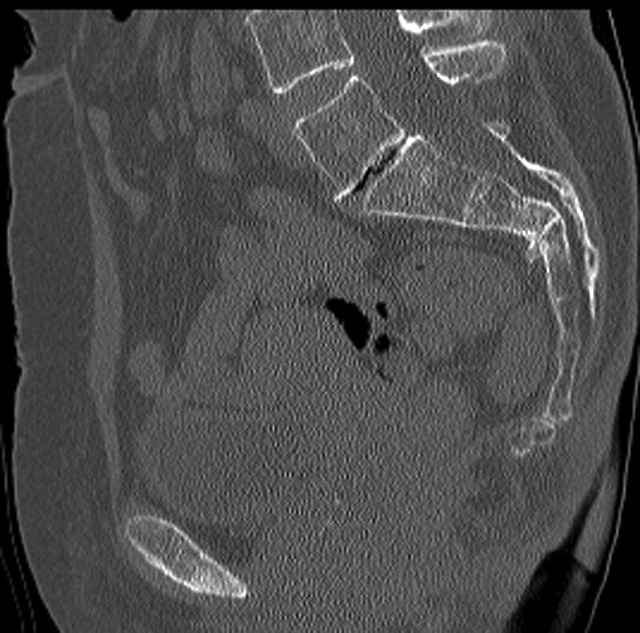

Here are a recent patient’s example slides...

54 yo Female Fell c/o Pain

Initial Films

?Instability on Exam - Limited by Pain

NonOp Initial Mgmt

3 Months After Fall

Continued Pain & Immobility

(+) Instability to Compressive Manual Exam

Pelvic CT Scan - 3 Months After Fall

Sacral Injuries

Ramus Fractures

Percutaneous Fixation

(B) Ramus-Retrograde

2 TransIliac-TransSacral

Upper Segment